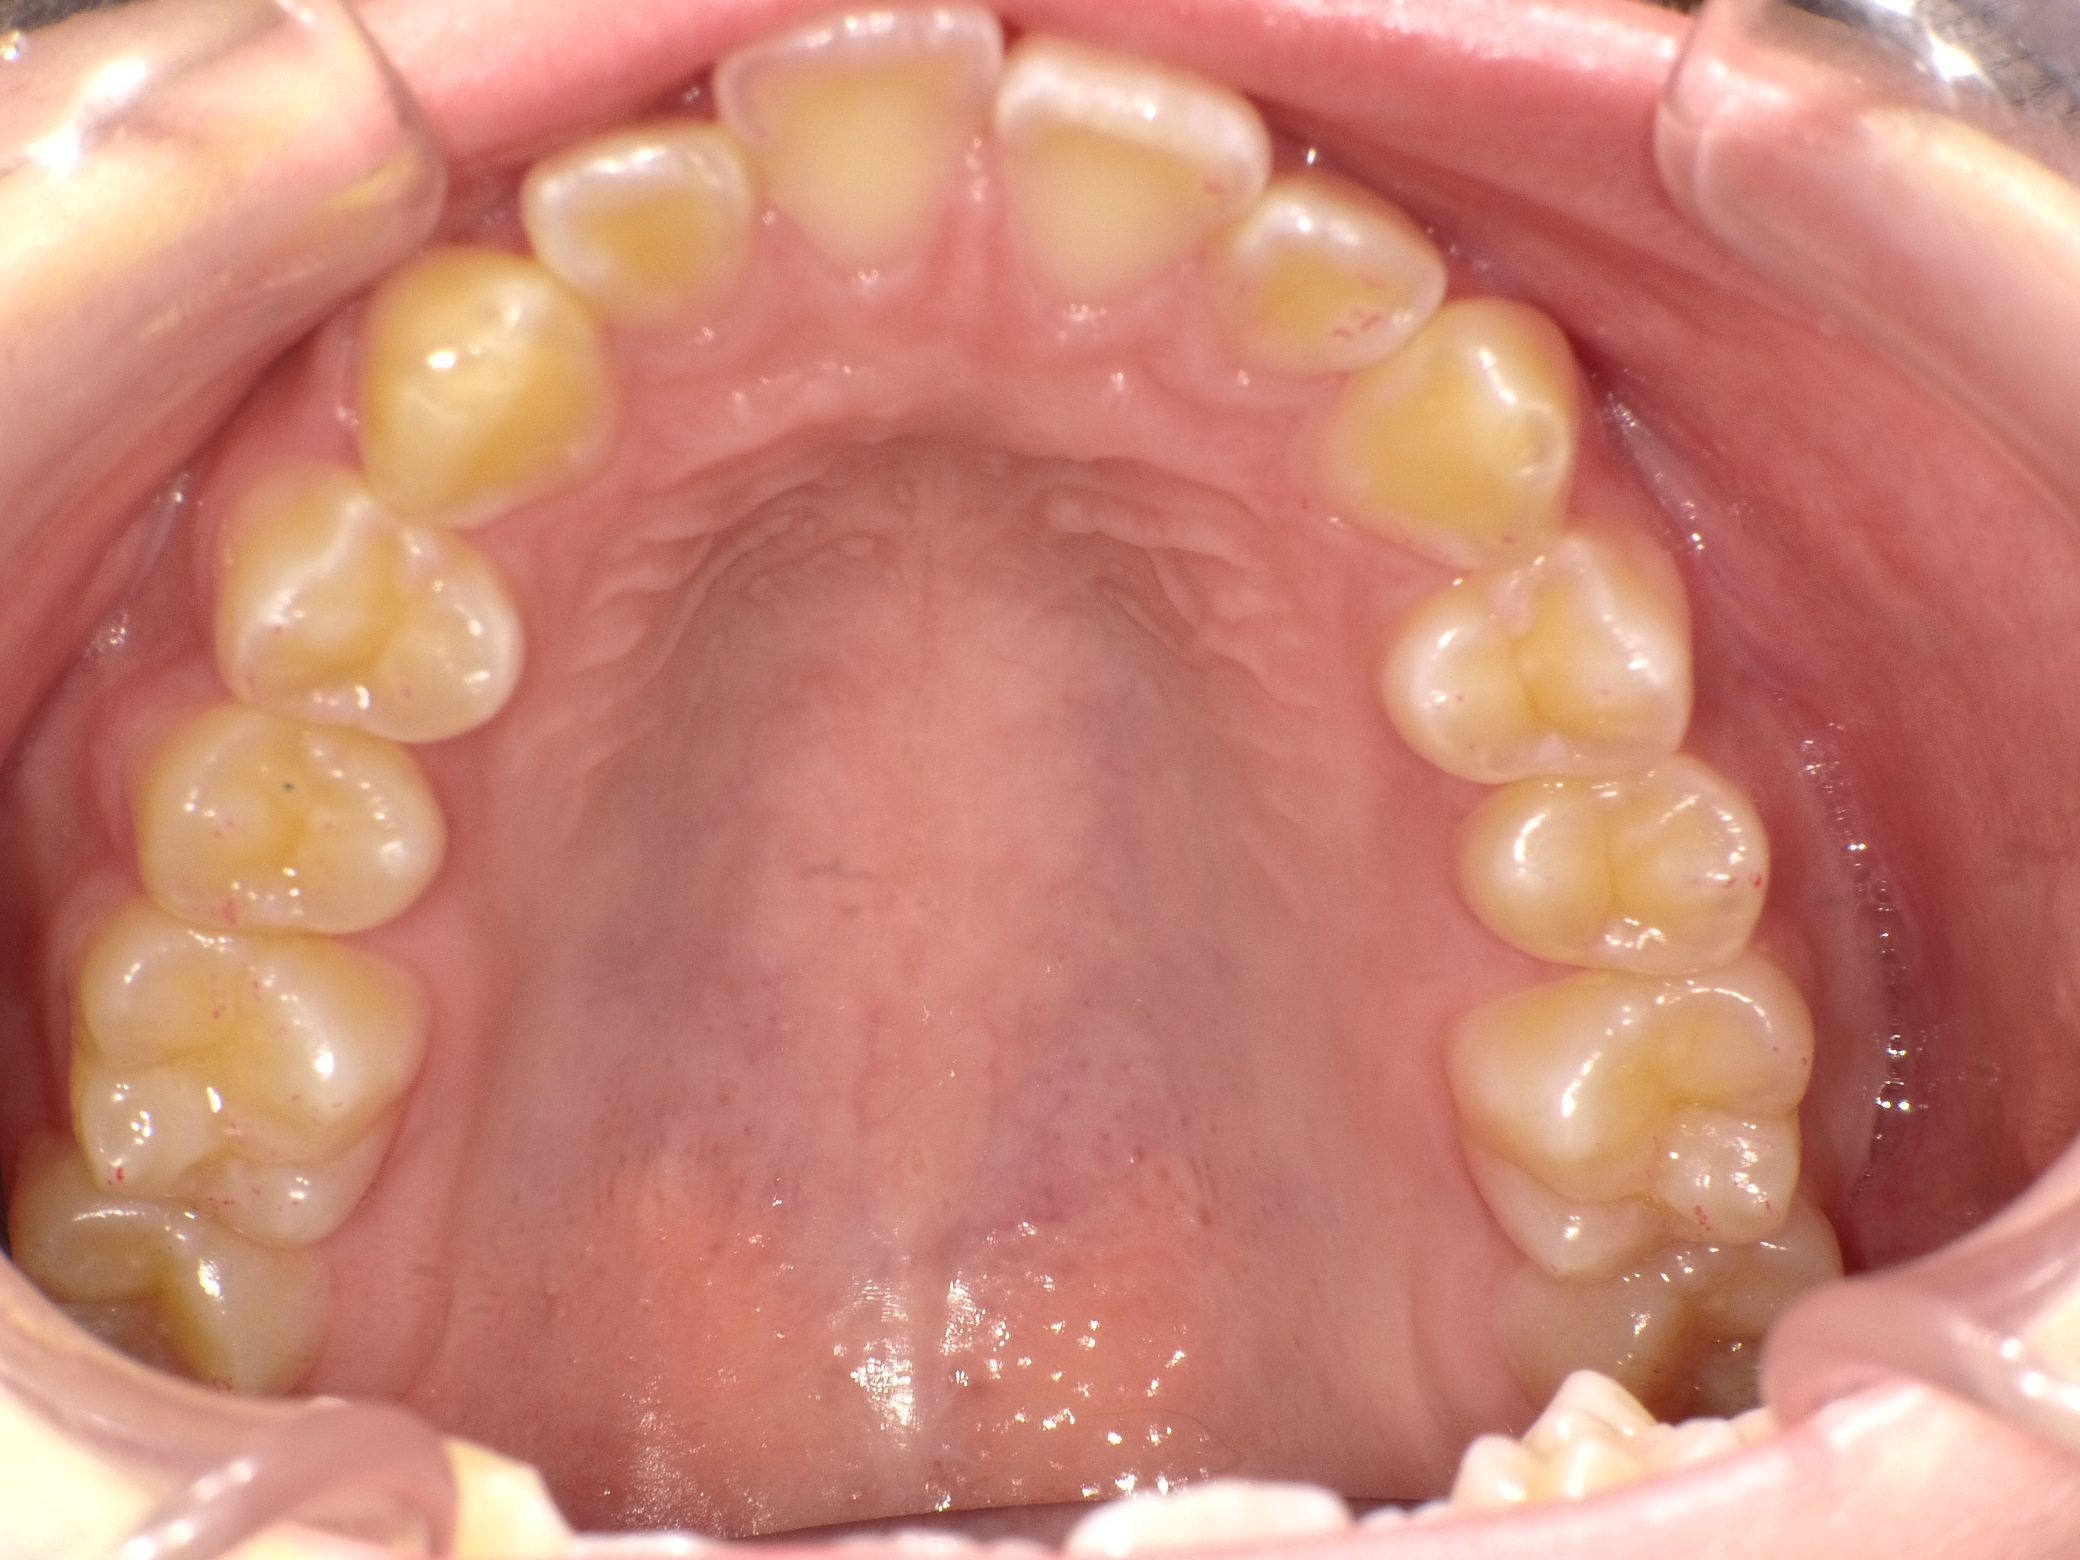

Before

After

【中学生】インビザライン矯正 叢生(ガタガタ)と上顎前突(出っ歯)を改善

でこぼこ

出っ歯

非抜歯

2期治療のみ